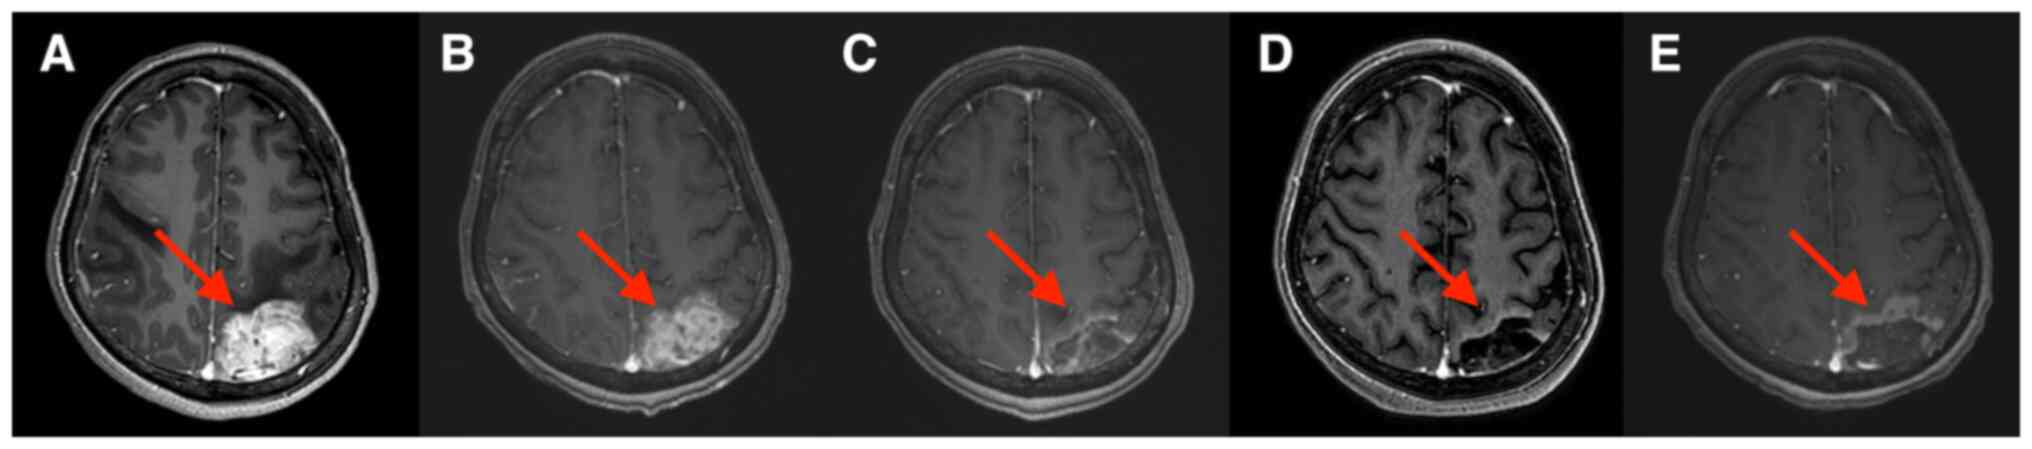

Although human epidermal growth factor receptor 2 (HER2)‑targeted therapy significantly improves the prognosis of patients with HER2‑positive breast cancer, most patients with advanced breast cancer eventually progress due to drug resistance. At present, there is no standard treatment after patients become resistant to HER2‑targeted therapy. Previous studies have indicated that anti‑angiogenesis drugs have potential efficacy in the treatment of advanced breast cancer. The present study reported on a case of a pretreated patient with HER2‑positive advanced breast cancer with brain metastases who developed resistance to multiple lines of HER2‑targeted treatment. The patient was treated with apatinib combined with trastuzumab and albumin‑bound paclitaxel. The patient achieved partial response to the third‑line treatment with a progression‑free survival of 9 months. After combination treatment, the symptoms of headache and vomiting were relieved and all the brain metastases were significantly reduced. The present case indicated that apatinib may have anti‑tumor activity in patients with HER2‑positive breast cancer with HER2‑targeted drug resistance. The present case provides valuable information and may offer a new possibility for the treatment of patients with breast cancer with brain metastases who progressed after clinical treatment with small‑molecule anti‑HER2 tyrosine kinase inhibitor drugs.

Figure 2